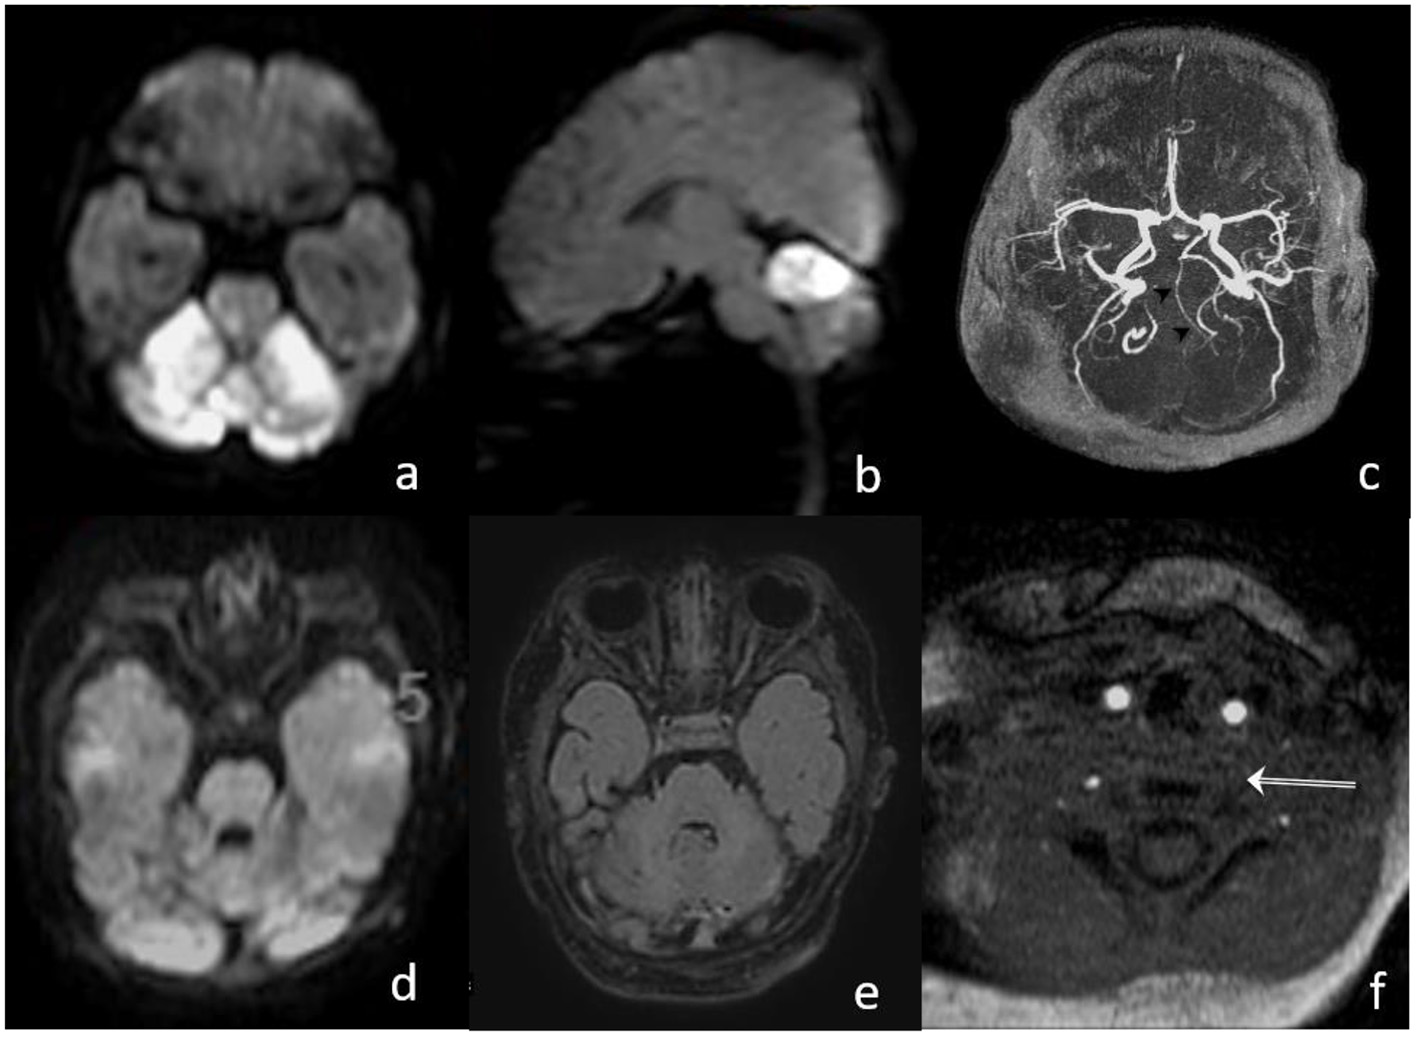

Magnetic resonance imaging (MRI) including MR angiography was performed 4 h after the onset of the symptom, demonstrating a distal basilar artery (BA) occlusion with bilateral lesions on diffusion-weighted imaging (DWI) in the territory of the superior cerebellar artery (Figure 1), and a very small and circumscribed brain stem lesion in the medulla oblongata.

Figure 1

Magnetic resonance imaging (MRI) before intervention. (a,b) TOF shows the stop of flow signal in the distal basilar artery (arrow in a and double arrow in (b), and a discontinuous flow signal in the proximal basilar artery (arrowheads); (c) diffusion-weighted imaging (DWI) MRI signal elevation and ADC decrease (d) in the cerebellum corresponding to SCA territory without significant FLAIR changes (e). Only small diffusion restriction in the brain stem (medulla oblongata).

Six hours postintervention, doppler ultrasound confirmed the recanalization of the BA with antegrade perfusion, and 24 h follow-up MRI angiography showed patency of the BA with a regular flow profile. There was no increase in the volume of DWI abnormalities (Figure 3). After the extubation, the clinical condition was stable with intermittent mild declines in oxygen saturation for 2 days. Medical therapy was continued with phenobarbital for 14 days and with nimodipine for 7 days, respectively, to prevent seizures and vasospasm. Additionally, enoxaparine was started once daily as an individual treatment, with a likely proximal left vertebral artery occlusion or low flow. The patient was discharged from our hospital on day 17, after the stroke with normal motoric patterns and with no neurological deficits.

Figure 3

(a,b) MRI on day 1, after the intervention, shows bright DWI lesions in both SCA territories with small brain stem involvement; (c) TOF proves patent hypoplastic basilar artery; (d,e) MRI on day 15 shows normalization of DWI signal and decrease in the FLAIR lesion in the cerebellum; and (f) missing proximal flow signal in left VA.

Postinterventional follow-up imaging with MRI (day 1 and 15) and a transcranial ultrasound showed a proximal occlusion of the left VA, which had been catheterized during the intervention (Figure 3f). In an etiologic stroke workup, a small atrial septal defect was confirmed by a cardiac ultrasound. Clinical follow-up examination 30 days after the stroke showed a normal neurological examination.